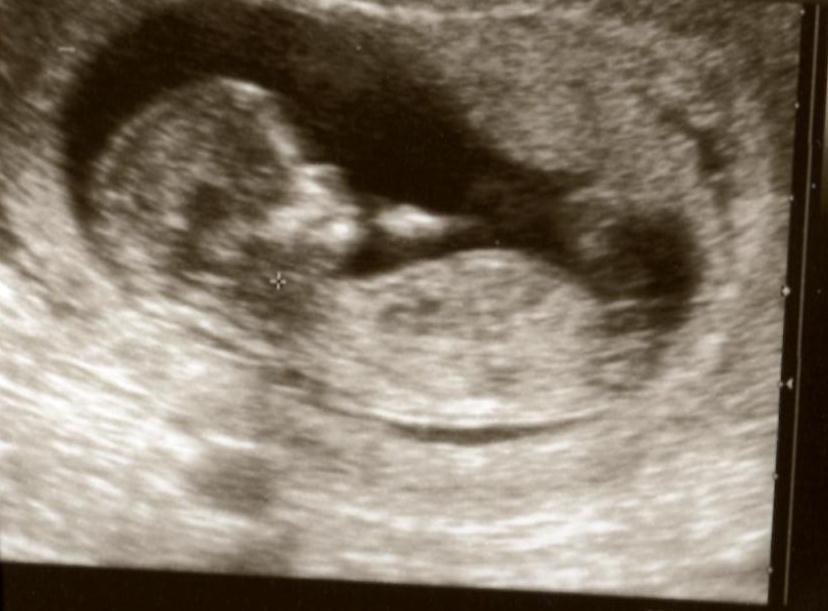

Hoping for a girl this time, was looking for some hope from my 12 week scan photo's?

I am not even sure if you can see a nub ... but any guesses would be much appreciated (I have also posted in the gender ultrasound section ... so apologies if you have looked twice)

If anyone can see a nub, could you please tell me where you are looking? Thanks so much ..

Attachment 2540